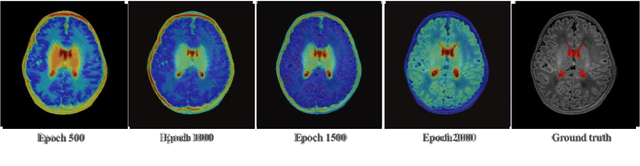

3D image segmentation is one of the most important and ubiquitous problems in medical image processing. It provides detailed quantitative analysis for accurate disease diagnosis, abnormal detection, and classification. Currently deep learning algorithms are widely used in medical image segmentation, most algorithms trained models with full annotated datasets. However, obtaining medical image datasets is very difficult and expensive, and full annotation of 3D medical image is a monotonous and time-consuming work. Partially labelling informative slices in 3D images will be a great relief of manual annotation. Sample selection strategies based on active learning have been proposed in the field of 2D image, but few strategies focus on 3D images. In this paper, we propose a sparse annotation strategy based on attention-guided active learning for 3D medical image segmentation. Attention mechanism is used to improve segmentation accuracy and estimate the segmentation accuracy of each slice. The comparative experiments with three different strategies using datasets from the developing human connectome project (dHCP) show that, our strategy only needs 15% to 20% annotated slices in brain extraction task and 30% to 35% annotated slices in tissue segmentation task to achieve comparative results as full annotation.